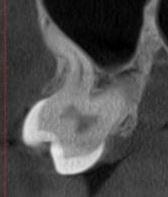

Коли коріння «ховає сюрпризи» - Корені зубів часто мають складну кривизну, гачкоподібні закручення або розгалуження, які на звичайному 2D-знімку накладаються один на одного, створюючи ілюзію прямого каналу. На плоскій картинці неможливо побачити реальний об'єм та напрямок вигину, що критично важливо при видаленні «зубів мудрості» або ендодонтичному лікуванні. КТ MyRay дає змогу лікарю заздалегідь побачити 3D-геометрію кожного кореня, оцінити його близькість до нижньощелепного нерва чи гайморової пазухи та підібрати правильну тактику роботи. Це мінімізує ризики поломки інструменту в каналі або травмування сусідніх структур, перетворюючи складну хірургію на прогнозовану процедуру.

КТ дозволяє провести віртуальну операцію: встановити імплант у програмі, виключивши будь-які ризики травмування пацієнта.